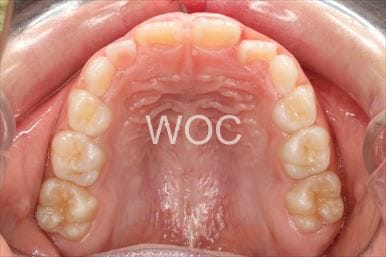

叢生

治療前1

治療前2

治療前3

治療前4

治療前5

- 年齢:7歳9ヶ月

- 主訴:スペースがない、デコボコしている

- 診断名:叢生、上顎前突、過蓋咬合

- 装置:可撤式拡大装置、機能的矯正装置

- 期間:4年1ヶ月 ※

- 費用:基本矯正料金:380,000円